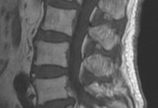

【骨质疏松】导航微创手术治疗骨质疏松性椎体压缩骨折与腰椎滑脱

病情概述: 女性,69岁;腰痛伴左下肢疼痛1年半,外伤后加重1个月。患者1年半前无明显诱因出现下腰痛伴左下肢放射性疼痛,为左侧腰部、臀部、大小腿外侧至左足第二足趾背侧疼痛、麻木,疼痛为间断性出现,严重时有刀割样疼痛感觉,休息后可缓解。伴有间歇… [详情]